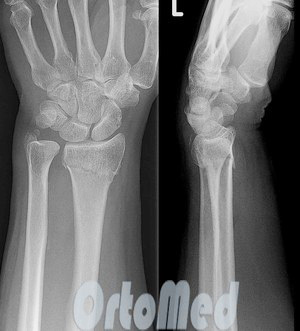

После все это на следующий день пошли в дет. поликлинику и сделав рентген узнали что на лучевой кости правой руки трещина

Примерно такая(фото не моё). Её еле видно.